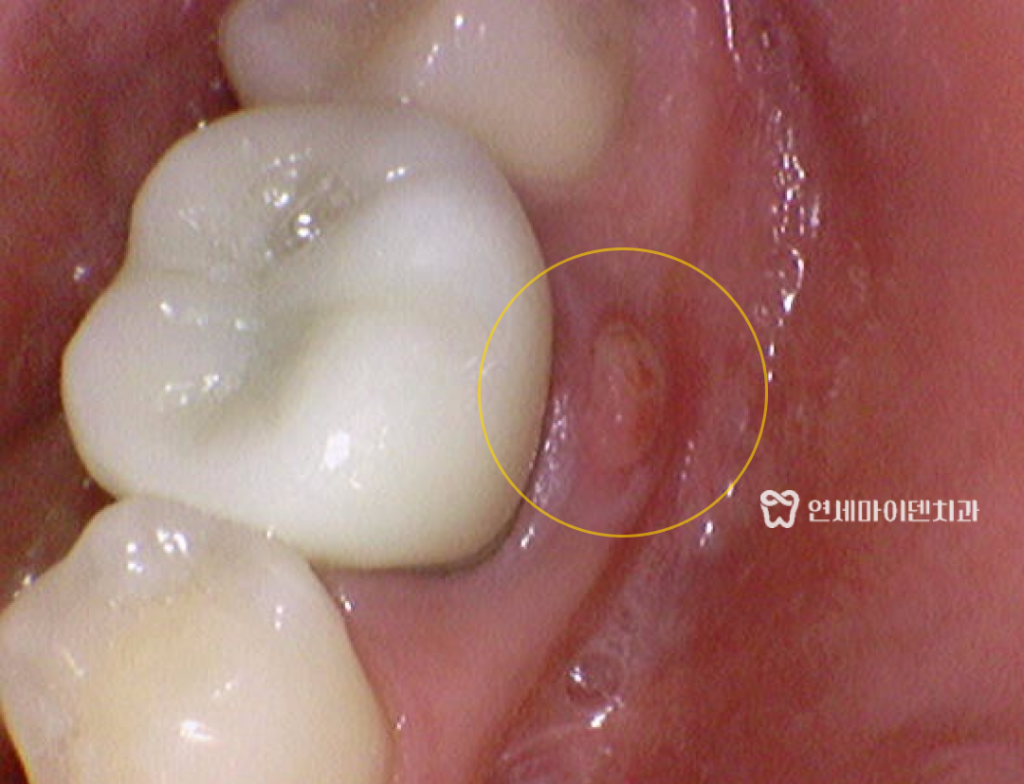

이번 치료의 주인공은 20대 후반의 남성 환자분이셨습니다.

이전에 한 번 신경치료를 받았던 치아의 잇몸이 붓고

잇몸 고름이 생겨서 다른 치과에 먼저 방문하셨다고 합니다.

검사 결과, 문제의 치아는 아래 어금니 36번 치아였고

잇몸 근처에 검게 보이는 염증 소견이 있었습니다.

놀랍게도 2주 만에 잇몸에 났던 고름

잇몸 여드름이 말끔히 사라졌습니다.